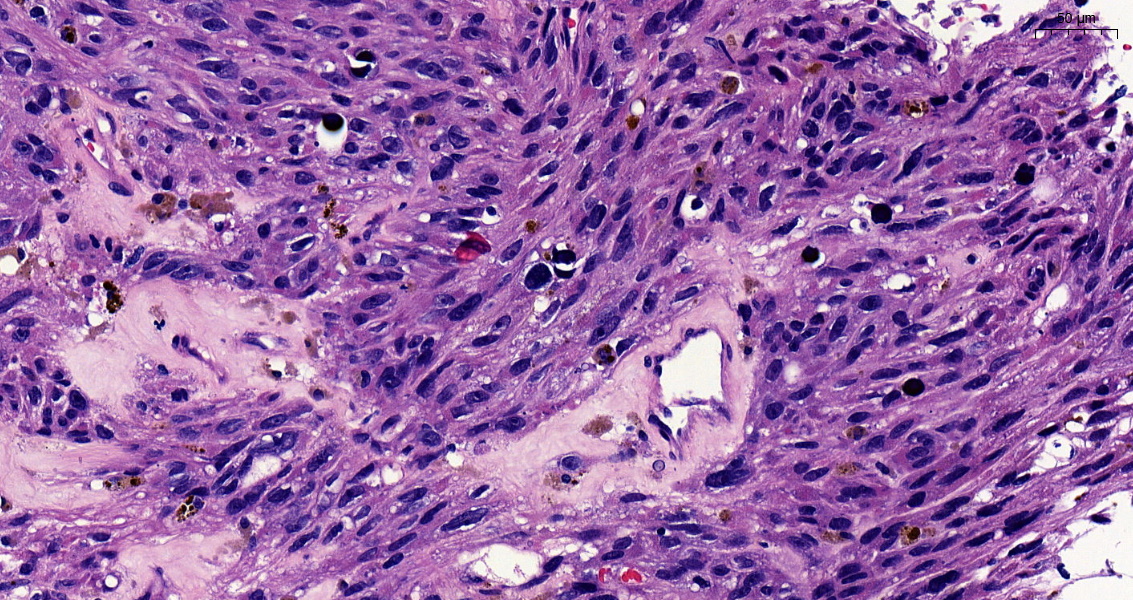

Incidental lung tumor... pulmonary hamartoma with unusual morphology?... what is your opinion? (2⃣) #PathTwitter #pulmpath @smlungpathguy @SansanoValero @yro854 @natasharekhtman @mkbaine @atman_ci @Path_Matt

angelpanizo1's tweet image. Incidental lung tumor... pulmonary hamartoma with unusual morphology?... what is your opinion? (2⃣) #PathTwitter  #pulmpath @smlungpathguy @SansanoValero @yro854 @natasharekhtman @mkbaine @atman_ci @Path_Matt